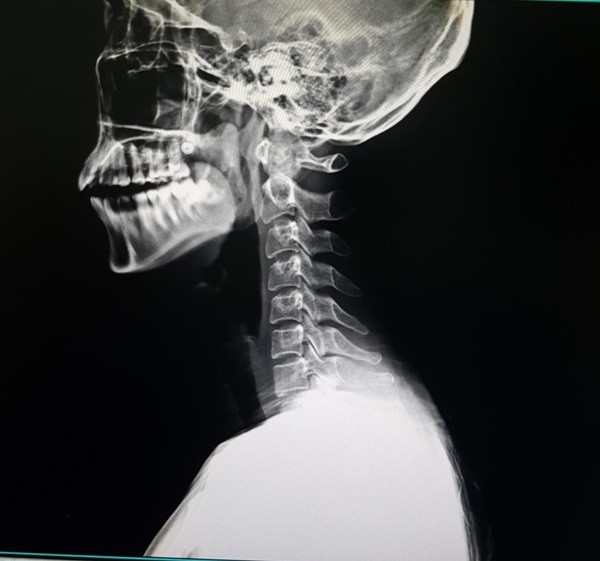

목디스크가 있는지는 진단법을 이용해서 직접 판단해볼 수 있다. 가장 먼저 디스크가 생겼을 경우 손가락이 둔감해져서 섬세함이 줄어든다. 그러므로 글씨 쓰기가 힘들거나 단추 잠그는 게 어려우면 목디스크 초기증상을 의심해야 한다. 또한 젓가락질이 힘들고 동그라미를 똑바로 그리지 못하겠다면 목디스크일 확률이 높다. 또 디스크가 생겼을 경우 목에서 팔까지 내려가는 신경을 누르면서 어깨부터 손까지 쥐가 난다. 어깨, 손에 난 쥐가 만세 자세를 하면 통증이 사라진다면 디스크 때문일 수도 있다. 실제로 목 디스크 환자가 병원 방문 시 팔을 머리위로 올린 채 진료실에 오는 사례가 보인다. 또 목 디스크가 오면 힘이 약해지기 때문에 손가락의 마디 한개마다 힘이 안들어간다. 그러므로 손가락을 붙이면 20초를 못버티고 한 개씩 떨어진다. 또한 하체의 기능이 떨어지면서 휘청거리면서 걷게된다. 더 자세히 판단하고 싶으면 바닥에 일자를 그려놓은 다음 그 위를 걸어보자. 똑바르게 걷지 못하면 목디스크를 의심해야 한다.